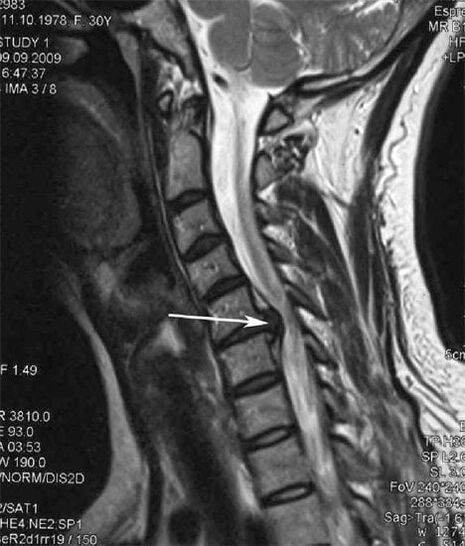

Бастапқы кезеңдерде, остеохондроз MRI көмегімен анықталады. Кейін патологияны радиографияны қолдану арқылы диагноз қоюға болады. Жатыр мойны омыртқасының радиографтарында омыртқалар арасындағы қашықтықтың төмендеуі, қырылықтардың патологиялық өзгерістері және остеофитоздар байқалады.

Көптеген адамдар кенеттен ауыр азапқа байланысты мойындарын өзгерте алмайтындығына шағымданады. Бұл құбылыс грыжа дискісінің пайда болуын көрсетеді. Артқы, мойын және жоғарғы аяқ-қолдың ауырсыну себебі - жұлыннан пайда болған жүйке тамырларының бірін қысады.